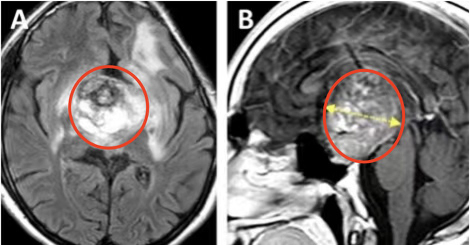

患儿4岁时,就曾因确诊丘脑毛细胞星形细胞瘤而接受开颅手术,手术并不彻底,因此术后他开始了两个周期的辅助化疗。然而,肿瘤在随后的12年内复发,患儿出现了全垂体功能减退和严重的左侧视力障碍,几乎等同于左眼失明。MRI显示鞍区-丘脑巨大肿瘤,侵犯累及左侧海马旁回和侧脑室的上部。肿瘤体积达68.1mm³,其深度为44.4mm(黄色虚线)。

根据患儿的病情、肿瘤生长及MRI影像特点,巴教授决定采用双冠状皮肤切口、双额骨瓣开颅、经基底纵裂入路进行肿瘤切除手术。术后MR提示肿瘤近全切除,从而使患儿的视交叉和视神经束、垂体柄和下丘脑保持原样,极大保障了孩子之后的生活质量。